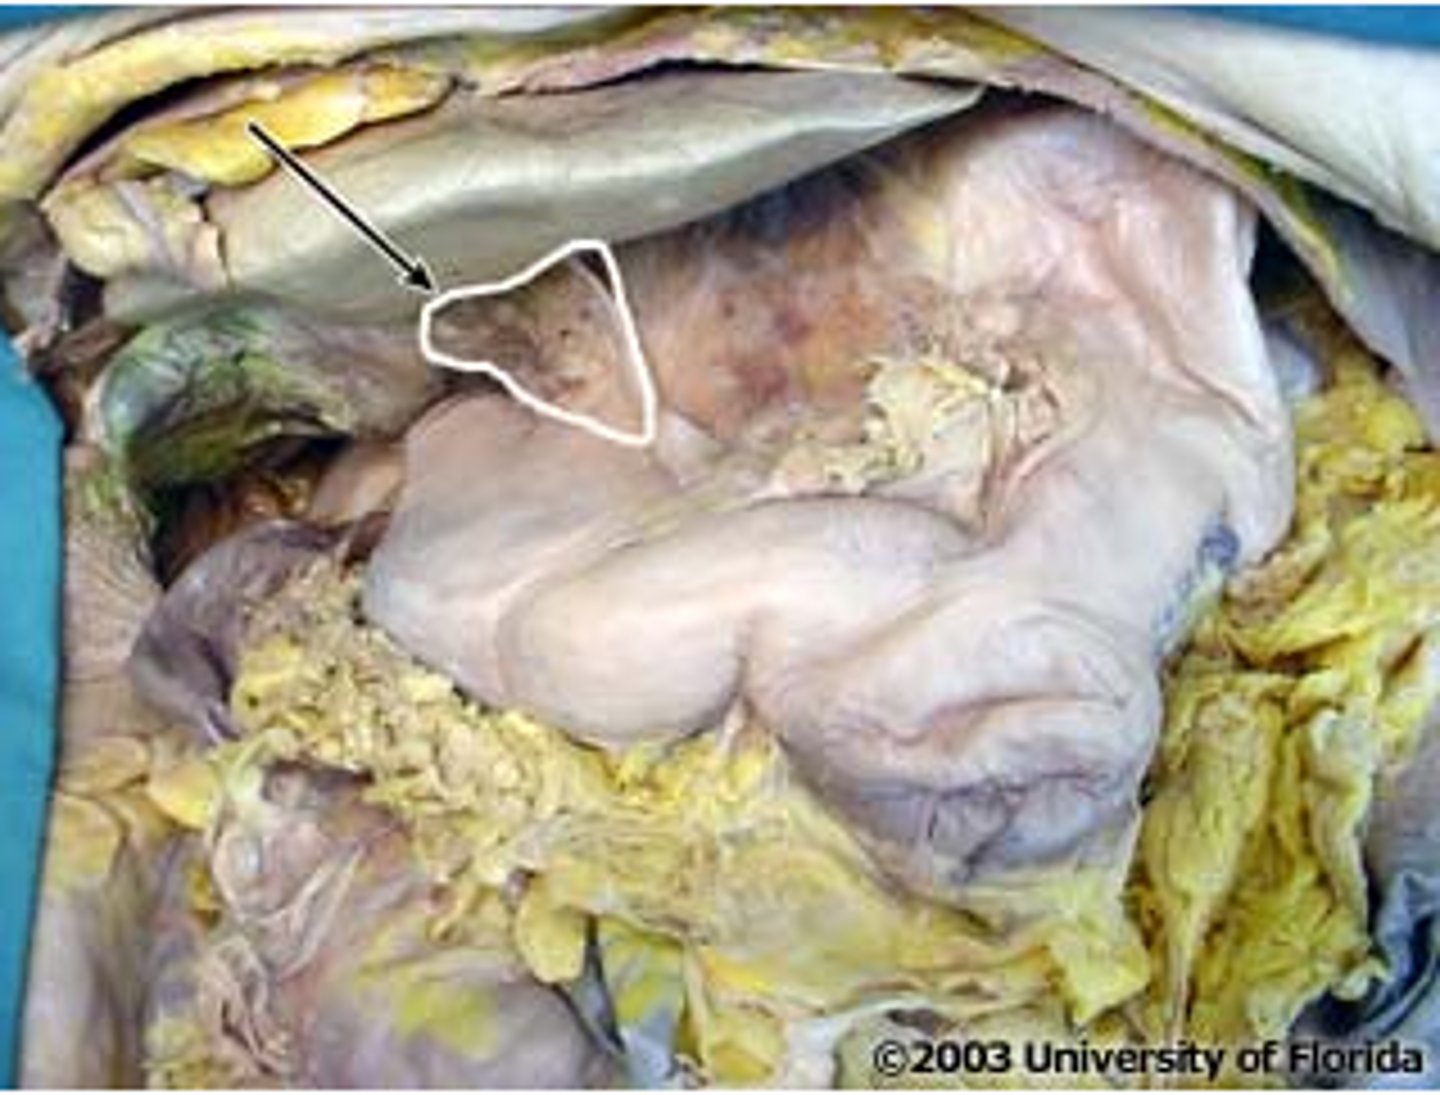

quadrate lobe (of liver)

caudate lobe (of liver)

porta hepatis

where the blood and lymph vessels, bile ducts, and nerves enter and leave the liver